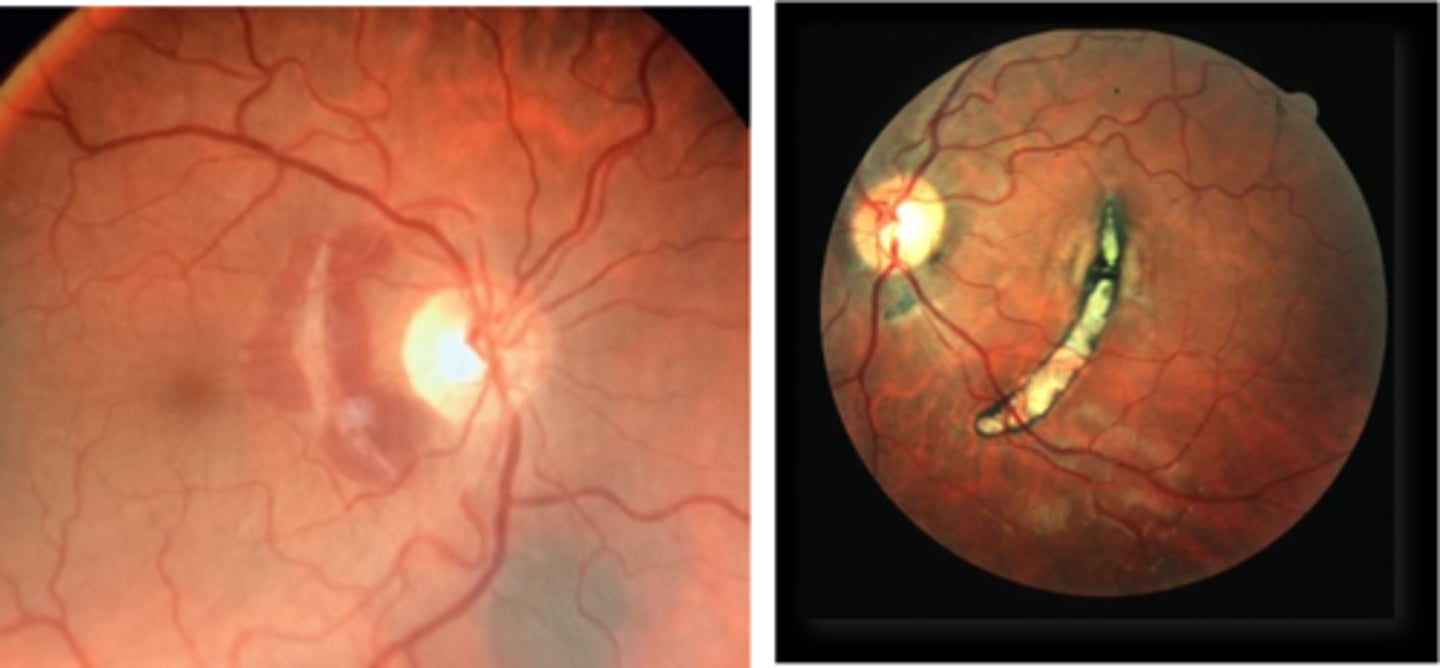

What finding of toxoplasmosis is seen in A/B?

retinitis turns into hazy scar with nerve pallor

What finding of toxoplasmosis is seen in C/D?

scarring overtime with VA loss/scotoma

What findings of toxoplasmosis are seen here?

retinal vasculitis

exudative scar

focal, hazy vitritis and retinitis

What findings of toxoplasmosis are seen here?

latent scars